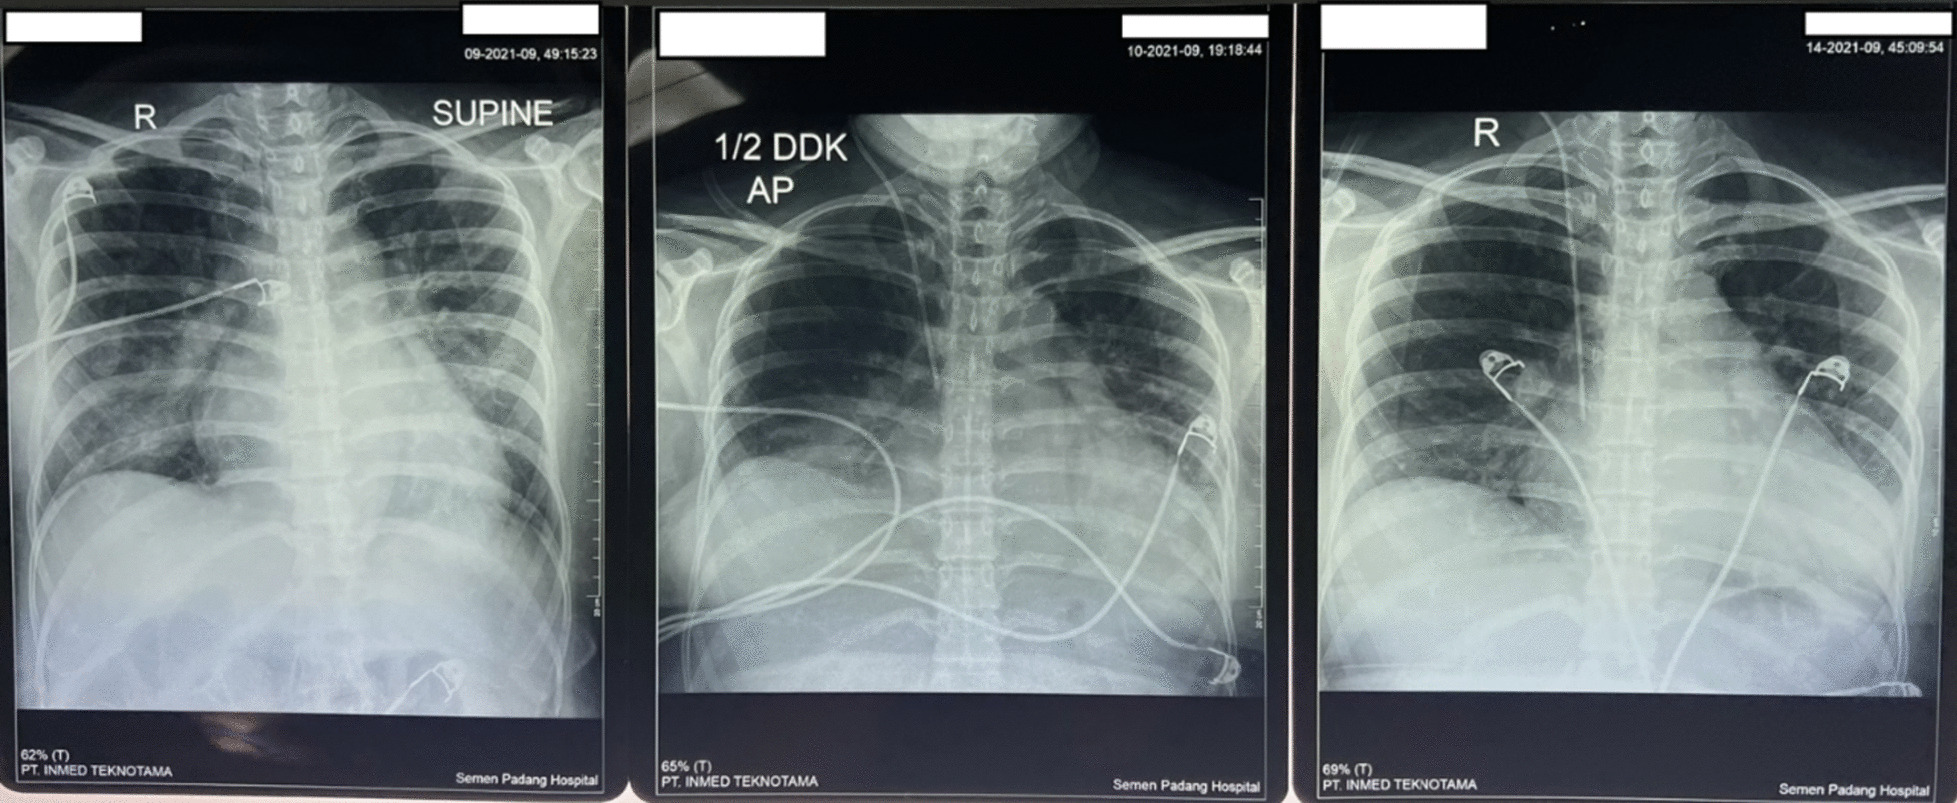

A 33-year-old Asian woman, in her third aterm pregnancy, ASA 2 with severe preeclampsia, was admitted to the ICU after caesarian section and tubectomy surgery due to shortness of breath and chest discomfort. The patient has a past medical history of severe preeclampsia in two previous pregnancies but no history of PPCM nor history of PPCM in her family, the patient also denied any history of congenital heart disease and history of heart failure. Her vital signs on ICU arrival were: blood pressure 136/92 mmHg, heart rate 150 beats/min, respiratory rate 38–40 breaths/min, temperature 38 ºC, saturation 95% with simple mask oxygen flow 6 L/min. She was awake and alert and was in a diaphoretic and tachypneic state. Lung examination revealed wet crackles throughout both lung fields. Her abdomen was diffusely tender. She had pretibial pitting edema. The neurologic examination yielded no abnormalities. Laboratory investigations at admission revealed white blood cell count was 20.300/mm3, hemoglobin and hematocrit were 13.6 g/dL, and 41% subsequently. Arterial blood gas analysis values on oxygen 6 L/min results were: pH 7.43; PaCO2 27 mmHg; PaO2 122 mmHg; PaO2/FiO2 ratio of 244; HC 17.7 mmol; BE − 3 mmol/L; SaO2 98%. PT and aPTT were within normal limits, but the D Dimer value was increasing by 1999 ng/mL. Serum Na+ was 137 mmol/L; K+ 3.5 mmol/L; calcium total 9.9 mg/dL; ureum 25 mg/dL; creatinine 0.4 mg/dL; SGOT and SGPT within normal limits but her bilirubin values were increased (total 3 mg/dL; direct 2.5 mg/dL, indirect 0.5 mg/dL) and lactate 3.3 mmol/L. The electrocardiogram (ECG) showed sinus tachycardia with nonspecific ST-T wave changes. The chest X-ray examination showed cardiomegaly with increased interstitial markings (Fig. 1). Echocardiography revealed all chamber dilation with marked global hypokinesis, decreased systolic function of left and right ventricles, mild–moderate mitral regurgitation, with an ejection fraction of 22% (Fig. 2).

Fig. 1.

Chest X-ray examination (left: post operative day 0, middle: post operative day 1, right: post operative day 6)